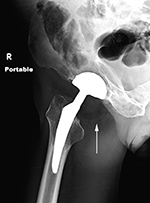

Metal-on-metal left hip arthroplasty with Metallosis and bony erosions |

68 year-old woman with left hip metal-on-metal prosthesis. Bony erosions (arrows) are evident on the greater and lesser trochanter from probable metallosis with pseudotumor formation. |